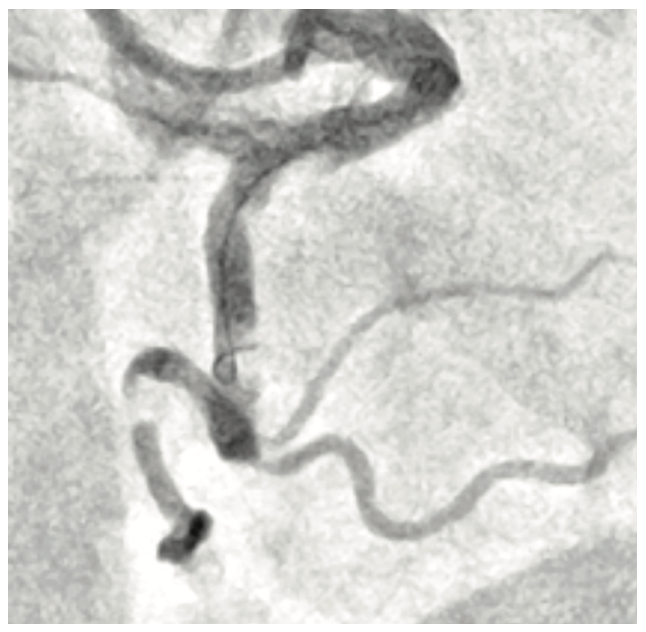

The RCA was engaged with the AL1 7 French (Fr) guide catheter via the right radial approach. After administering heparin to a goal ACT of >250s, we advanced a floppy coronary wire to the distal PDA using a microcatheter and subsequently exchanged it for a supportive guidewire. The loop did not unravel after placing the support wire and hence we introduced a 7 Fr guide catheter extension. We serially pre-dilated the lesions initially with a 1.5 mm x 15 mm, 2.0 mm x 20 mm TAKERU balloon catheter at 14 atm (Figure 3). We advanced the guide catheter extension further to the mid RCA using balloon catheter-assisted tracking and delivered several overlapping drug-eluting stents which were aggressively post-dilated with noncompliant balloons. Final angiography (Figure 4) showed no evidence of dissection or perforation. There was TIMI-3 flow and 0% residual stenosis. The patient was placed on triple therapy (aspirin 81 mg daily/clopidogrel 75 mg daily/apixaban 5 mg BID) for one month along with a proton pump inhibitor later dual therapy for 12 months.